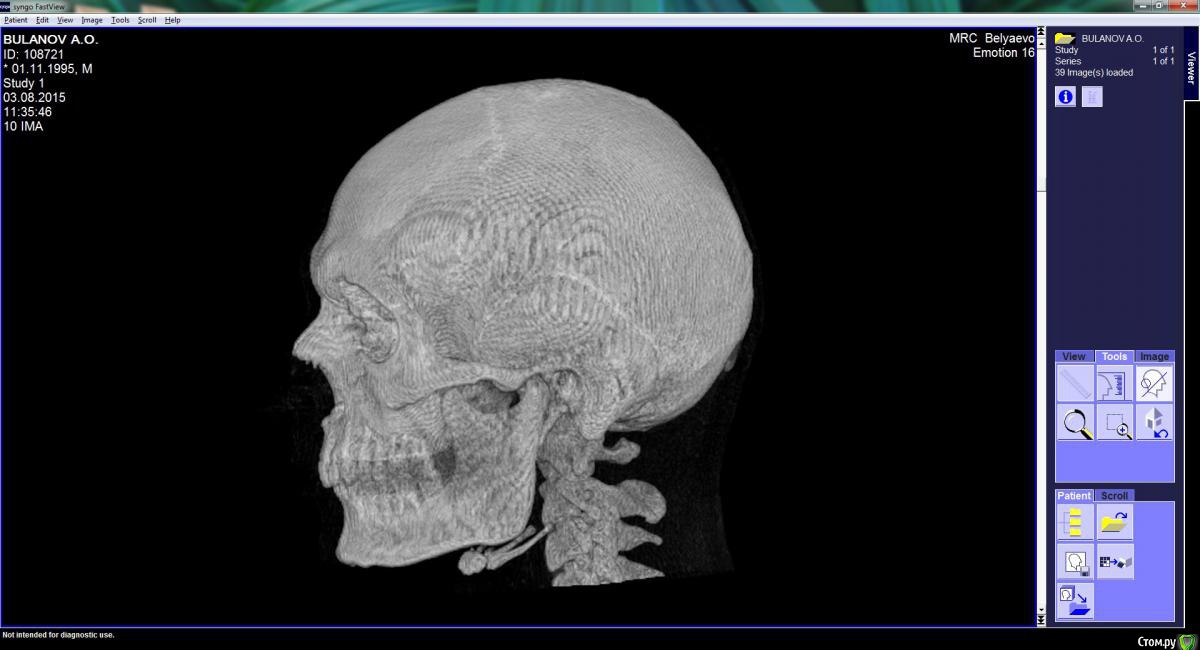

Arseny0111 Опубликовано 27 сентября, 2015 Поделиться Опубликовано 27 сентября, 2015 (изменено) Здравствуйте,в ходе драки получил удар,в верхнюю челюсть,сразу же не значительно сменился прикус и искривилась носовая перегородка.Есть ли на снимках отклонения от нормы?трещина?и т.д.Что с этим делать к кому обращаться?Из исследований дополнительно имеется МСКТ(3D)Спасибо. Изменено 27 сентября, 2015 пользователем Arseny0111 Ссылка на комментарий

Arseny0111 Опубликовано 1 октября, 2015 Автор Поделиться Опубликовано 1 октября, 2015 Здравствуйте,в ходе драки получил удар,в верхнюю челюсть,сразу же не значительно сменился прикус и искривилась носовая перегородка.Есть ли на снимках отклонения от нормы?трещина?и т.д.Что с этим делать к кому обращаться?Из исследований дополнительно имеется МСКТ(3D)Спасибо.Уважаемые доктора,помогите пожалуйста.Неужели нет компетентных специалистов в этой области? Ссылка на комментарий